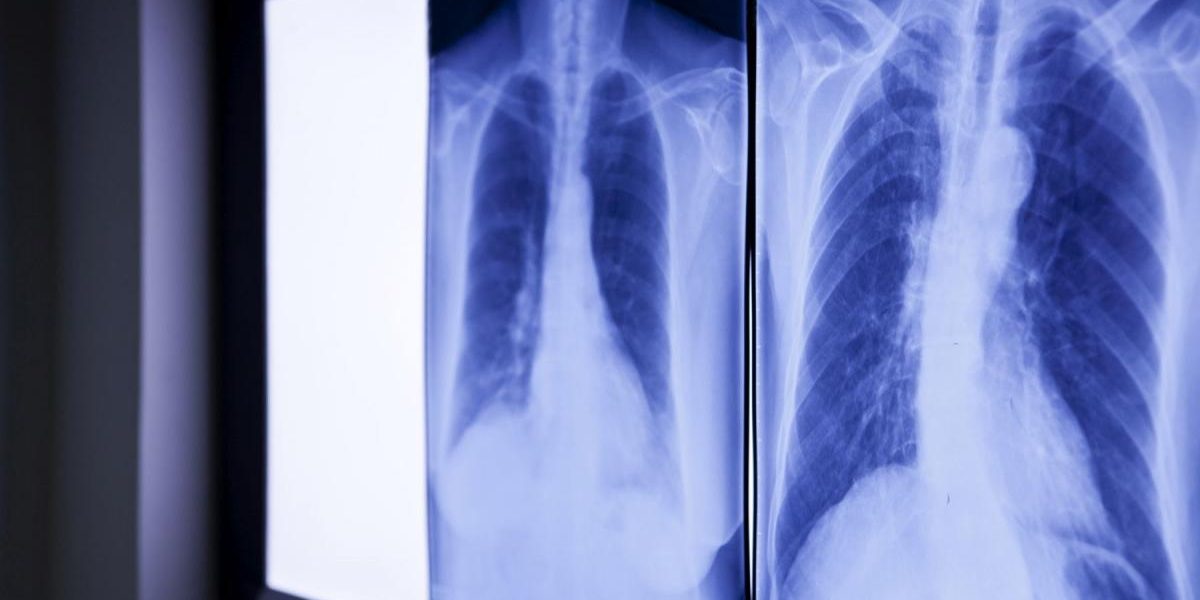

Bărbatul, identificat inițial ca Wang, s-a prezentat la spitalul din Wenzhou, acuzând dureri abdominale severe. Radiografiile au relevat existența unui obiect străin în duoden, suspectat a fi un termometru cu mercur. Doctorii au constatat că vârful acestuia apăsa direct pe peretele intestinal, ceea ce prezenta un risc major de perforație și hemoragie internă.